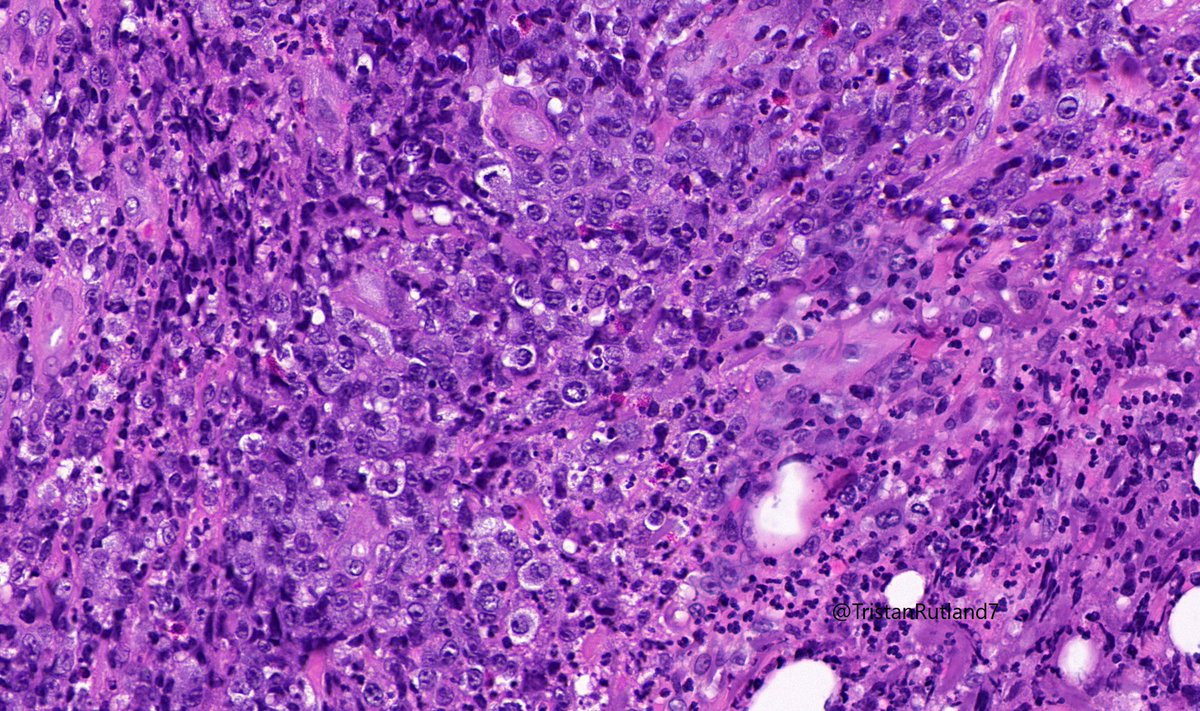

Female, adult, leg.

Large cell transformation of mycosis fungoides (MF).

3/ Large cell transformation is defined by greater than 25% large cells (4X size normal lymphocytes) or nodular aggregates in dermis.

4/ It usually arises from tumour stage (rare cases arising from patch stage have occurred).

6/ Differential diagnosis that need to be considered:

Primary cutaneous anaplastic large cell lymphoma (PCALCL)

Lymphomatoid papulosis (LyP)

Hx is absolutely essential in these situations (ie previous MF).

(?GATA3 may be helpful sometimes?).